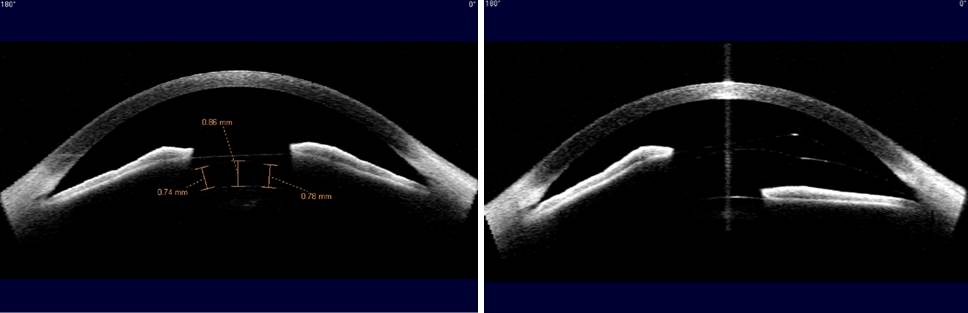

아래 비잔테 OCT 검사 이미지를 먼저 살펴보세요. 어떤 차이점을 발견하셨나요? 렌즈삽입술 후 외부 충격으로부터 주의하라고 늘 당부드리고 있는데요. 아래는 술자리에서 외상을 당하고 응급수술을 했던 환자의 Visante OCT 검사 결과입니다.

▼왼쪽이 다치기 전, 오른쪽이 다친 후, 왼쪽 홍채가 밀린 모양이 보이시죠?

아이리움에서 응급수술을 한 이 환자는 수술 후 아래와 같이 정상적인 모습으로 회복되었습니다.